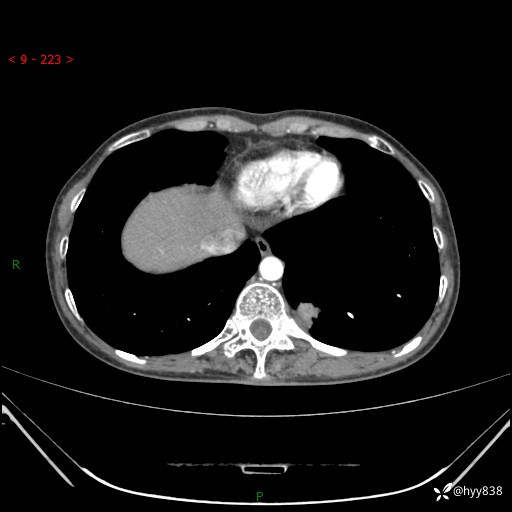

胸部CT平扫

增强动脉期+静脉期

各期CT值:48hu 65hu 76hu